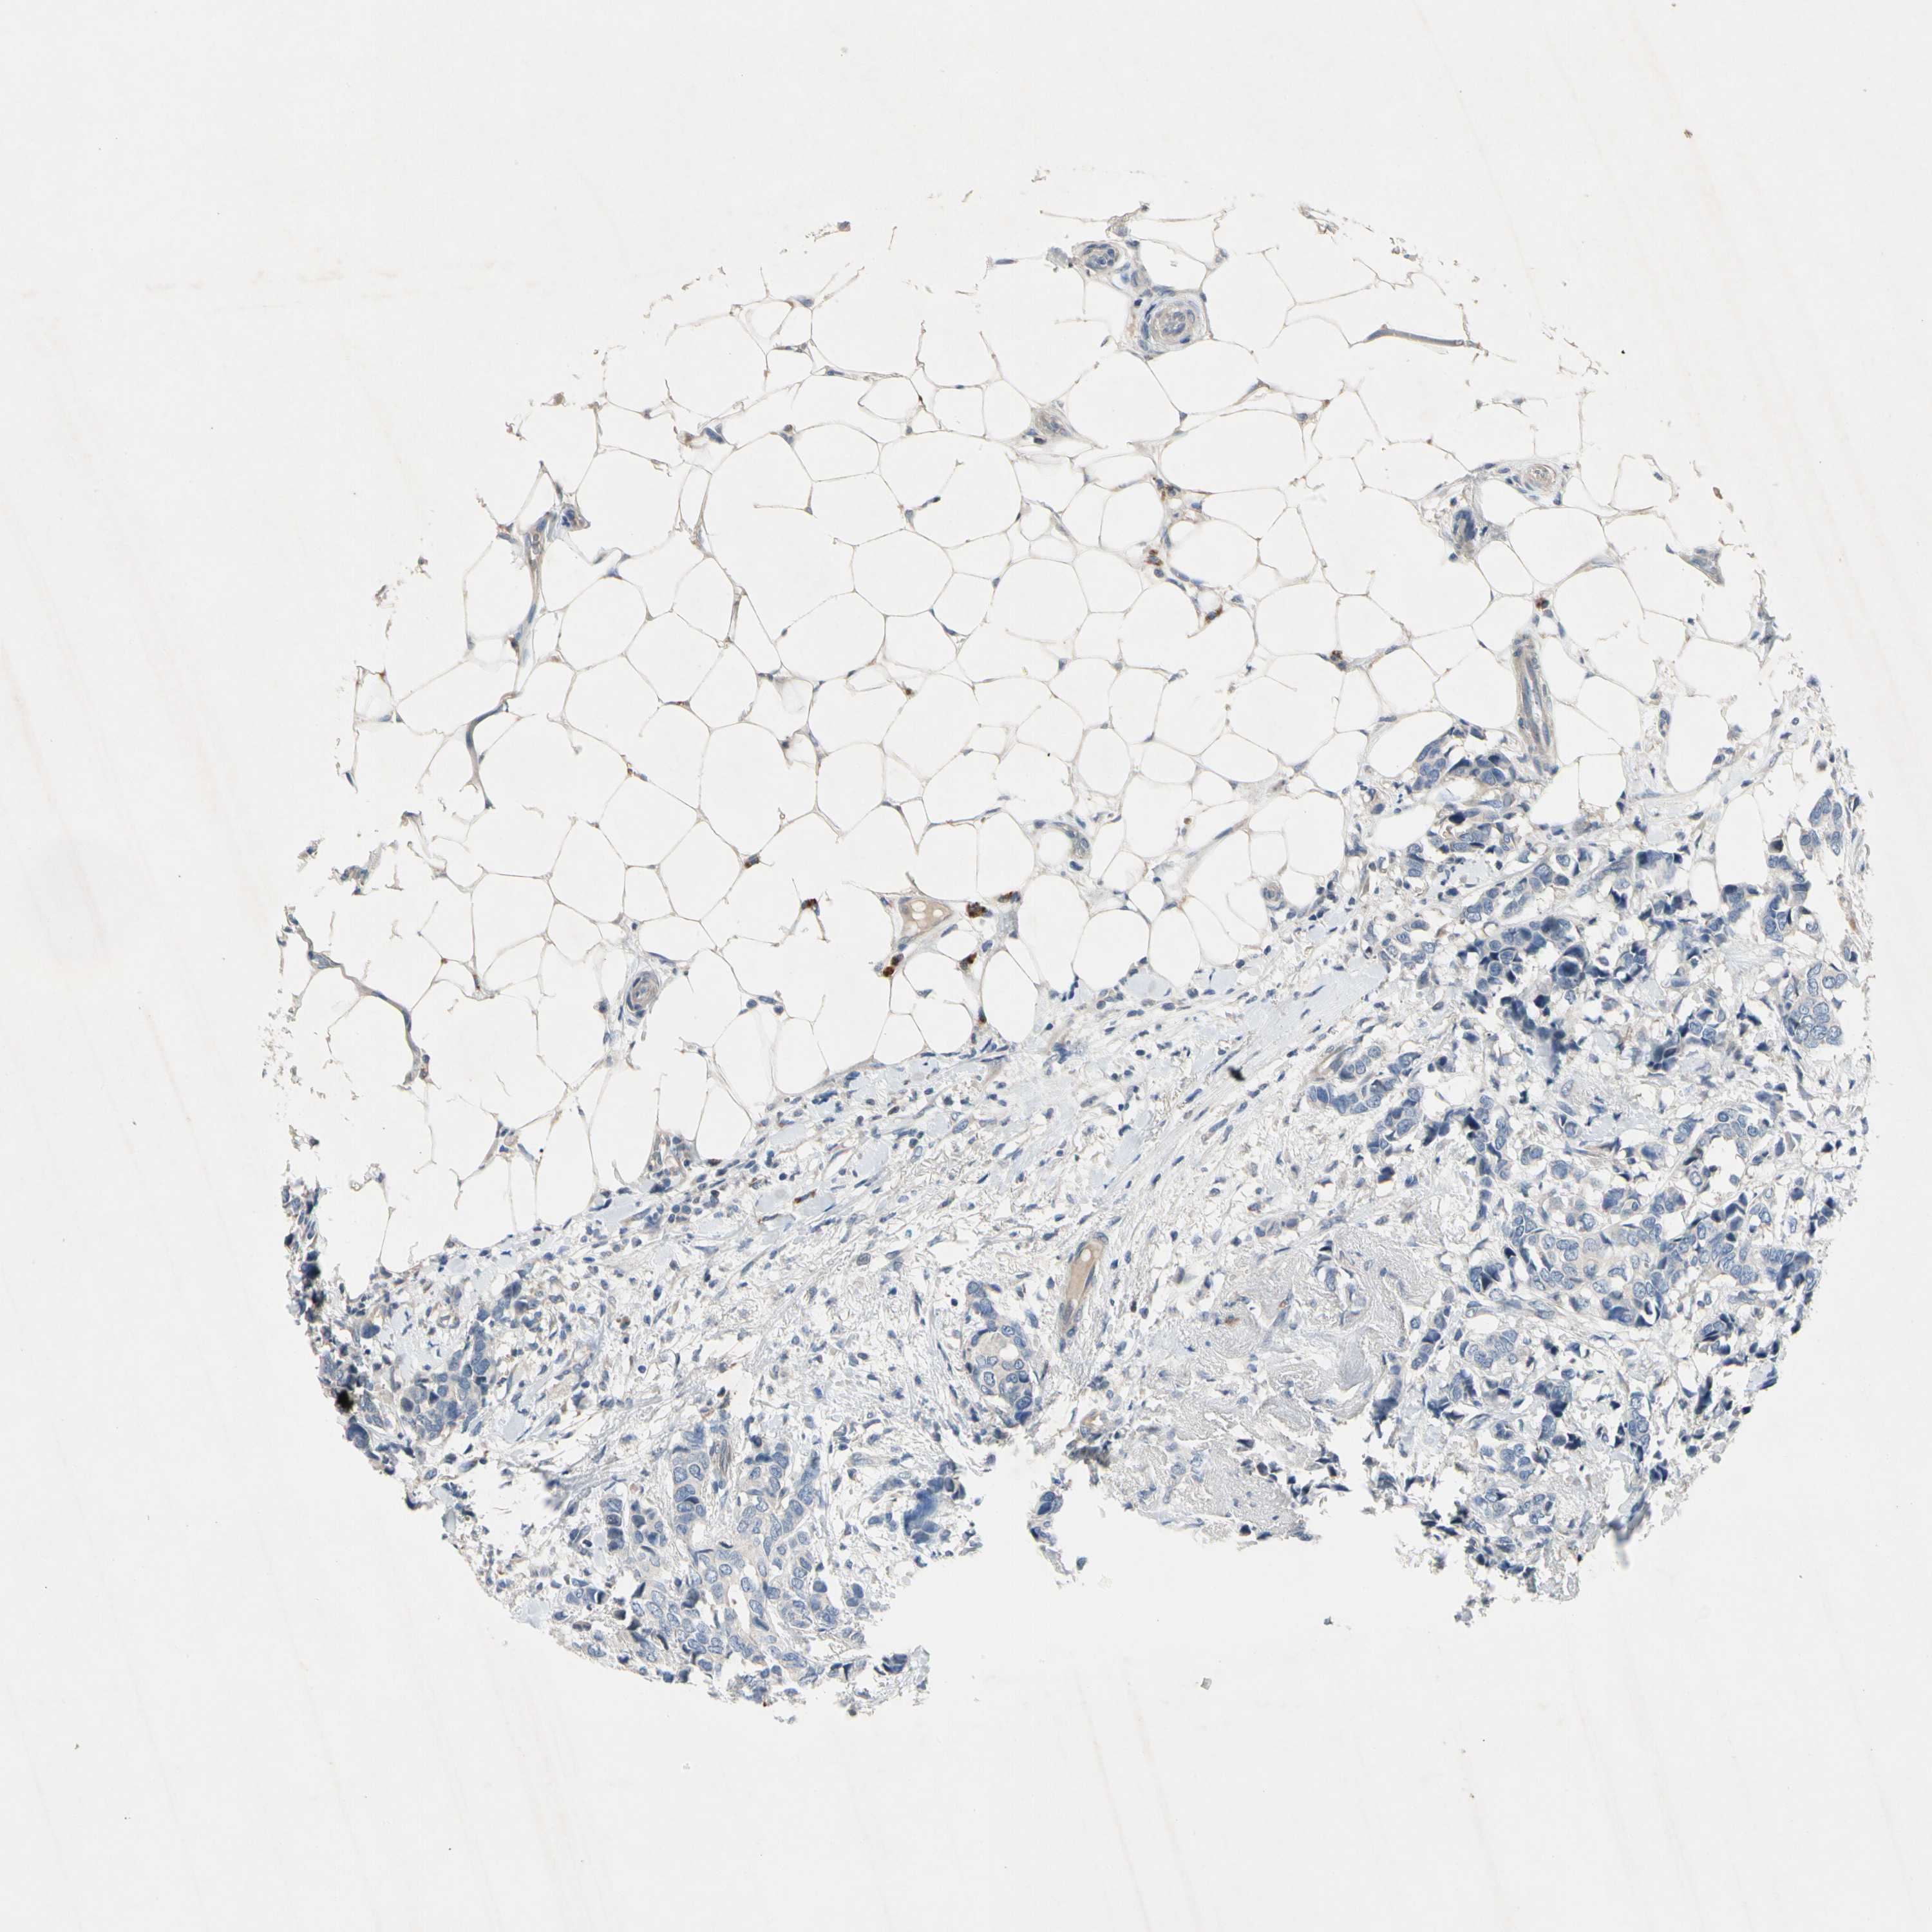

CANCER BREAST CANCER Show tissue menu

BRCA TCGA BRCA VALIDATION PROTEIN EXPRESSION

Breast cancer

Human cancer

Breast invasive carcinoma